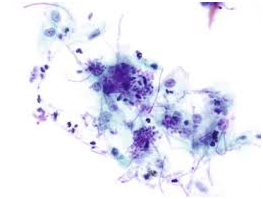

Figure 2 Periodic acid Schiff’s stain- Hyphae and spores.

Figure 3 Silver Methanamine (Grocott's stain)-Candida yeast and pseudohyphae.

Acute candidiasis: The distinguishing aspect is the presence of neutrophils in the stratum corneum. Disseminated disease expounds dermo-epidermal inflammatory infiltrate with intra-epithelial micro-abscesses.1,5 Fungal components are infrequent. Periodic acid Schiff(PAS), Silver Methanamine (Grocott stain- black fungal hyphae with a green environment and is specific for the deteriorating fungus ) aids in delineating the organism.1,5

Molecular analysis of Candida employs a Real time Polymerase Chain Reaction (RT-PCR). Monoclonal antibodies besides the Rapid agglutination tests (RLA) may also be applicable. Debatable conditions such as a “Candida Leukoplakia” mandate an evaluation of a histological specimen.1,6 Imprint smears and tissue material may be analyzed with the Periodic acid Schiff’s (PAS) stain. The carbohydrates in the fungal cell wall stain magenta. Gram Positive reactivity on Gram’s stain may be elucidated by the micro-organism.1,2,5